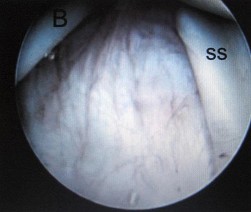

A 31-year-old volleyball player presents with deep posterior shoulder pain. MRI arthrogram reveals a posterior labral tear with an associated large paralabral cyst extending into the spinoglenoid notch. Clinically, this patient is most likely to exhibit which of the following isolated motor deficits?

Explanation

The suprascapular nerve innervates the supraspinatus muscle before passing through the spinoglenoid notch. A cyst located strictly at the spinoglenoid notch will compress the nerve distally, causing denervation exclusively to the infraspinatus. This results in isolated weakness in external rotation, while abduction (supraspinatus) remains intact.